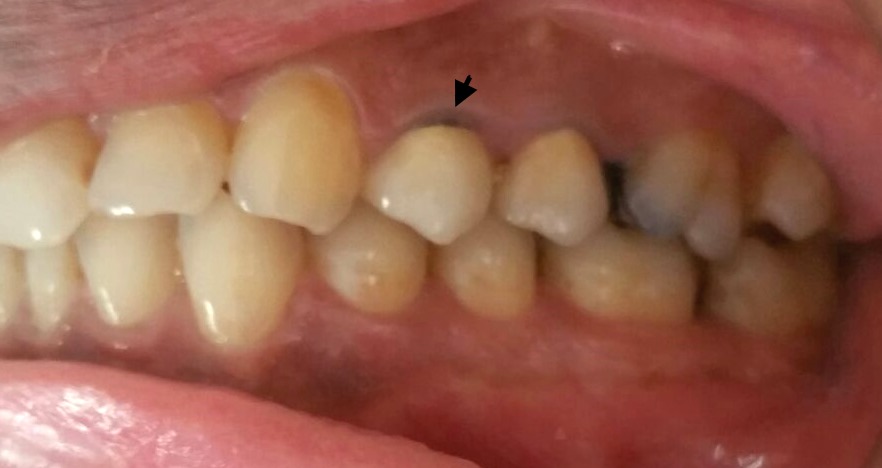

관교의치는 자연 치아를 대체하기 위해 고정적으로 부착되는 치과 보철물로, 지대치, 가공치, 유지 장치 등으로 구성된다. 가공의치는 심미성, 기능, 교합 안정성을 회복시키지만, 치아 삭제, 치수 손상, 이차 우식 등의 단점도 있다. 가공의치는 재료, 피개복 정도, 구성 형식, 내구성에 따라 다양하게 분류되며, 시술 과정은 평가, 치아 삭제, 인상 채득, 임시 수복물 제작, 최종 장착 및 검토 등으로 이루어진다. 실패 원인으로는 불량한 구강 위생, 기계적/생물학적/심미적 실패, 지대치 문제가 있으며, 정기적인 검진과 철저한 구강 위생 관리가 중요하다.

관교의치는 상실된 치아를 대체하여 심미성을 회복시켜주며, 특히 앞니 부위에서 그 효과가 두드러진다. 저작 및 발음과 같은 기능적인 측면을 회복시켜주고, 인접 치아나 맞물리는 치아가 기울거나 이동, 회전하는 것을 막아준다.[3] 또한, 과도하게 솟아오르는 현상을 방지하여 교합의 안정성을 유지하는 데 도움을 준다.[3] 이러한 장점들 때문에 환자들이 선호하는 치료 방법 중 하나이다.[3]

관교의치의 단점은 다음과 같다.- 치아 손상: 지대치를 삭제해야 하므로 치아 조직이 손상된다. 경우에 따라서는 상당한 양의 치아를 삭제해야 할 수도 있다.[3]

- 치수 손상: 치아를 삭제할 때 상아 세관이 열리면서 구강 내 세균과 치수 사이의 연결 통로가 생긴다. 깊게 삭제할 경우 치수에 손상을 줄 수 있다.[3]

- 이차 우식 발생: 크라운 변연 주변이나 탈락된 유지 장치 날개 아래에 이차 우식(충치)이 발생할 수 있다.[3]